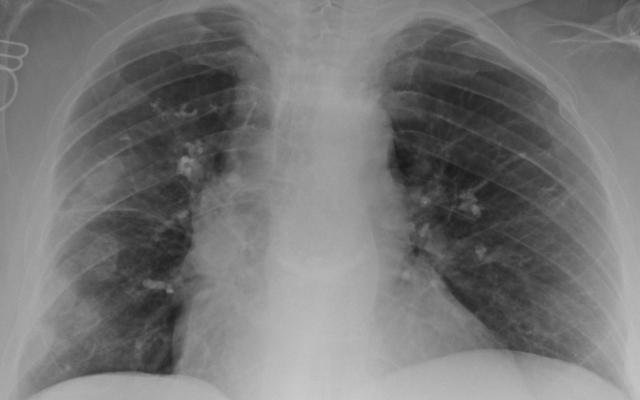

Een 59-jarige vrouw kwam op de Spoedeisende Hulp vanwege kortademigheid. Zij had ’s nachts een koude rilling gehad en een temperatuur van 38,9 °C. De voorgeschiedenis van patiënte vermeldde inzakkingsfracturen en ribfracturen. Bij lichamelijk onderzoek zagen we een niet acuut zieke vrouw met een temperatuur van 37,1 °C, een polsslag van 86/min, een ademhalingsfrequentie van 16/min en een zuustofsaturatie van 94%. Bij auscultatie van de longen hoorden wij beiderzijds midthoracaal lichte crepitaties. Bij laboratoriumonderzoek was de CRP-waarde 77 mg/l. Vanwege de verdenking op een pneumonie werd een röntgenfoto van de thorax gemaakt. Hierop werden meerdere scherp begrensde bolvormige structuren…